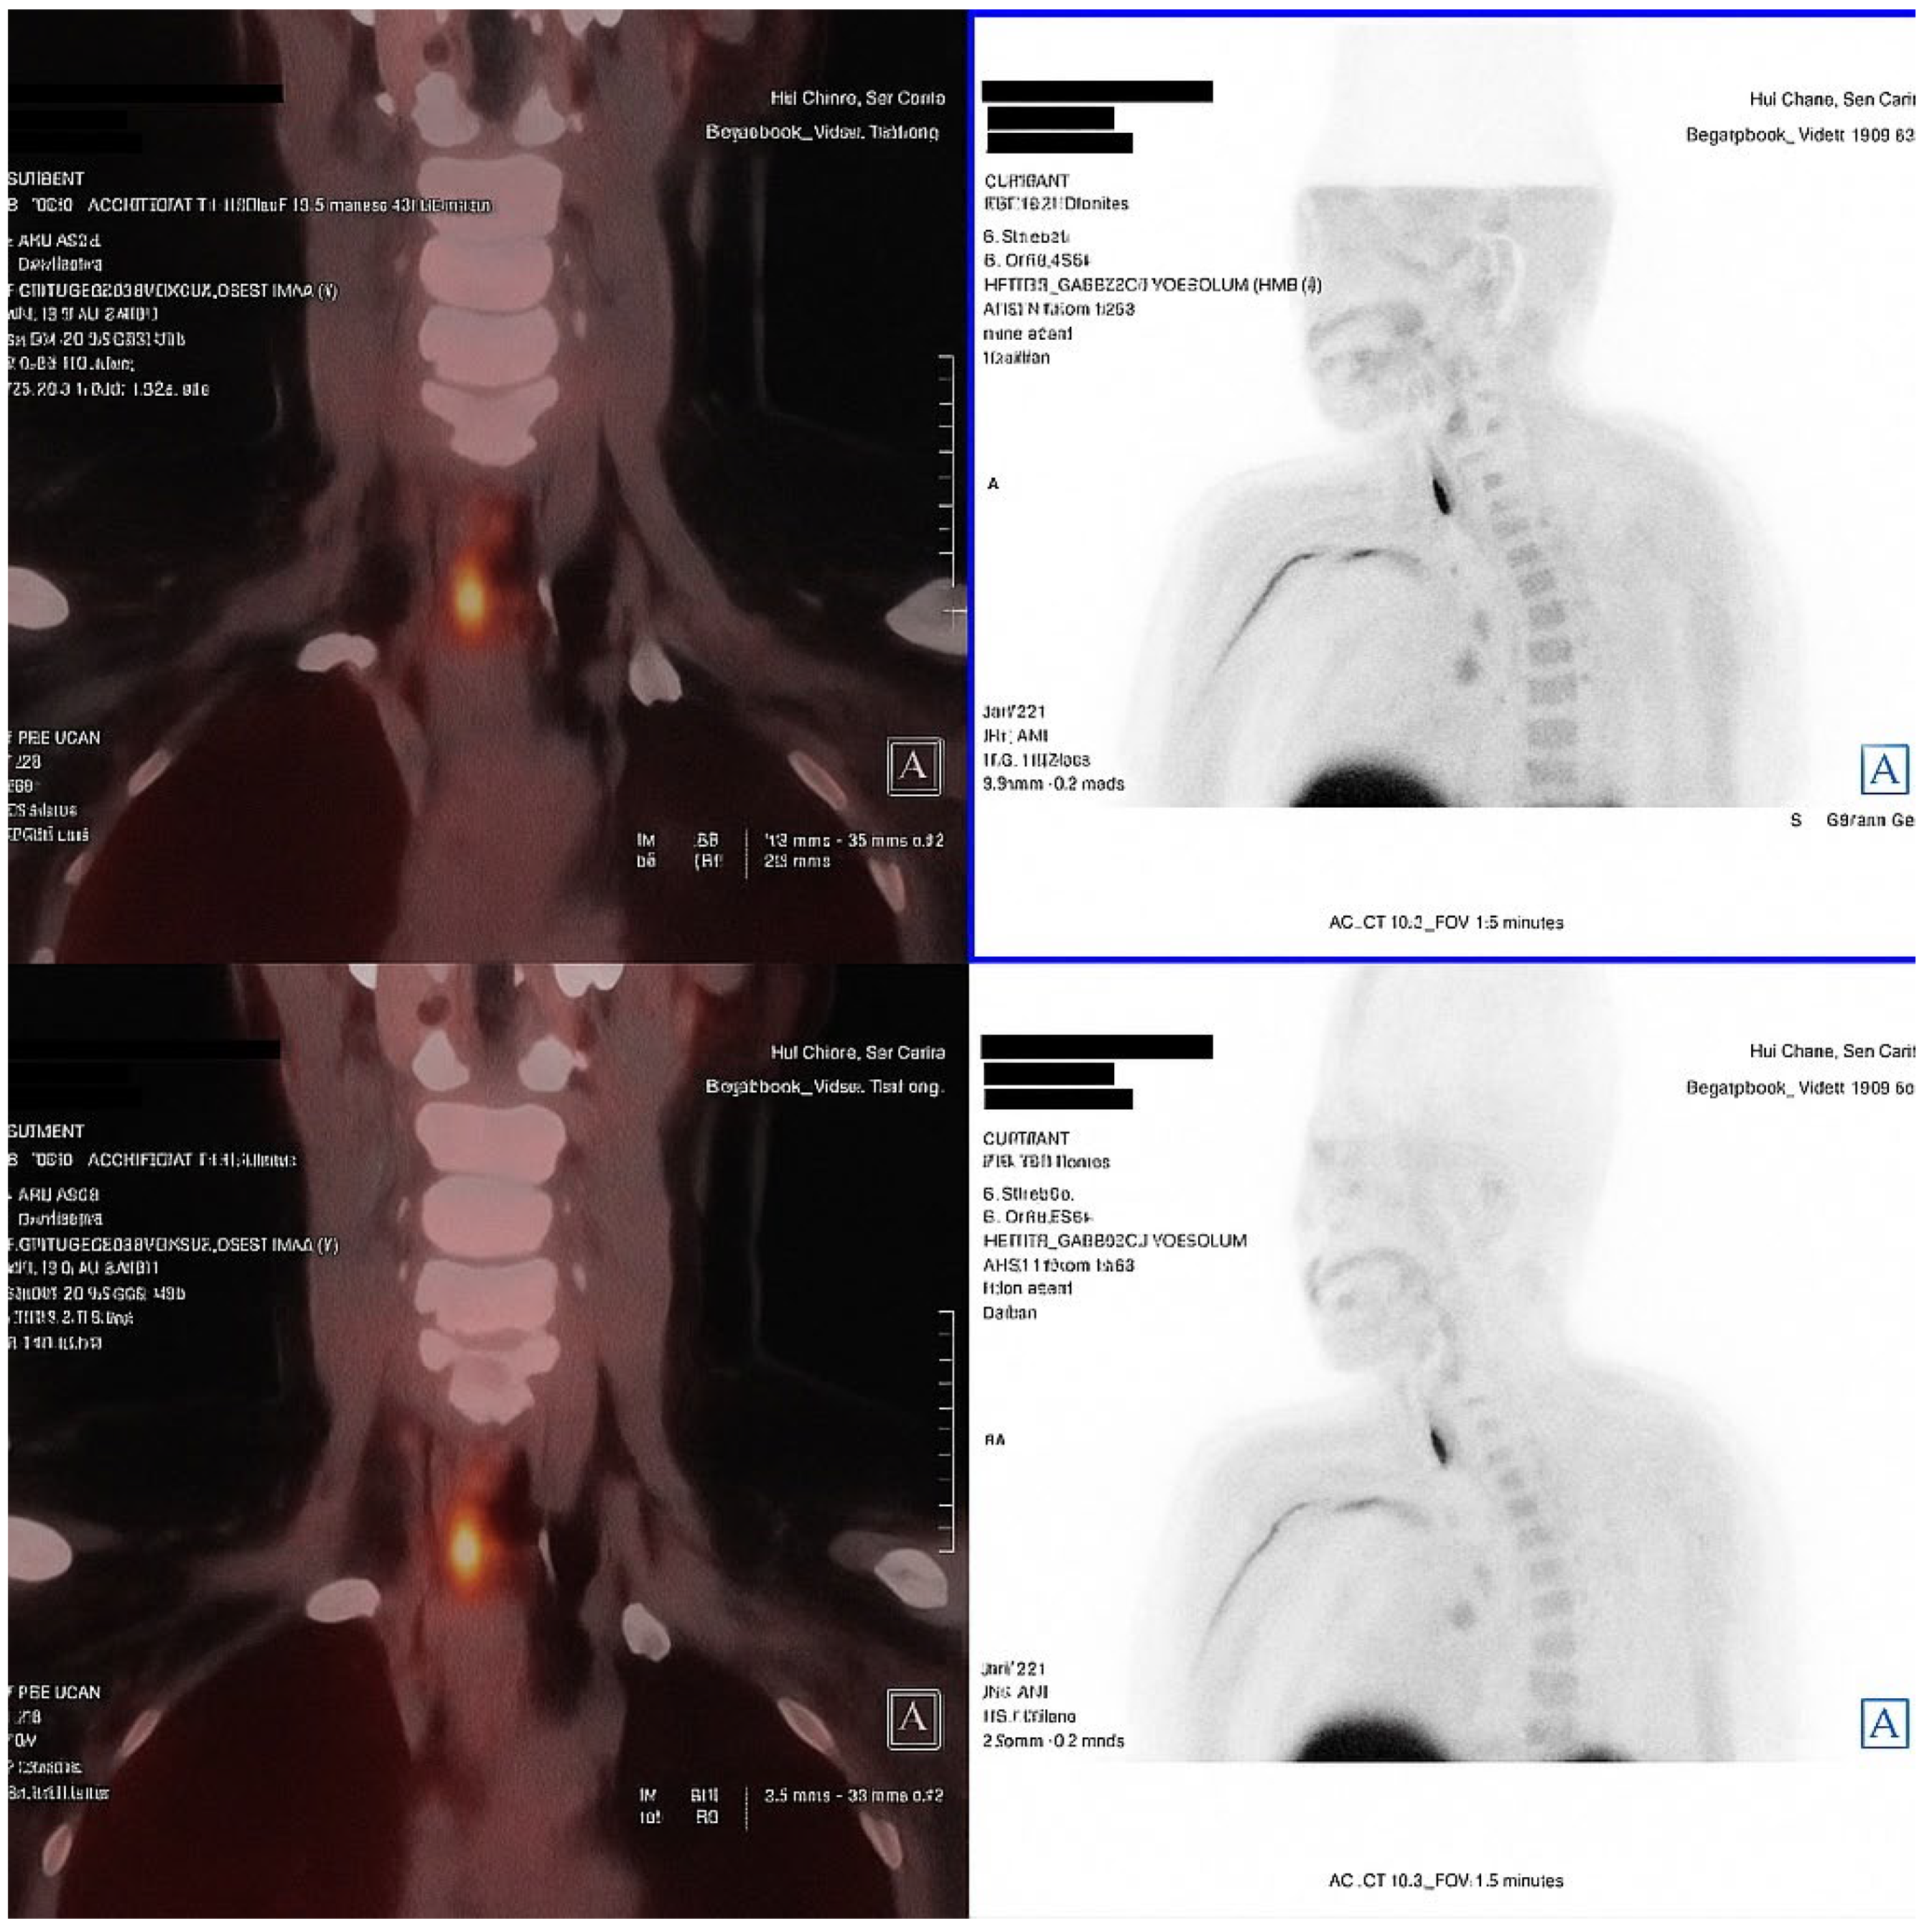

An 18F-fluorocholine PET-CT (18F-choline PET-CT) scan performed in November 2024 identified two right parathyroid adenomas, located in the upper and lower poles. The patient did not report renal colic, falls or new fractures. At the most recent follow-up, a diagnosis of PHPT was confirmed, characterized by hypercalcemia, persistent hypophosphatemia, elevated PTH and FGF-23 levels and absence of hypercalciuria or overt hyperphosphaturia.

Secondary causes of hyperparathyroidism, including vitamin D deficiency, chronic kidney disease, and malabsorption, were excluded, thereby supporting the diagnosis of primary hyperparathyroidism (PHPT) (Figure 1).

Figure 1. Fused coronal and axial images (left) and anterior projection MIP sections (right) identify two areas of focal increased uptake in the right cervical region. The uptake corresponds to a posterosuperior nodular lesion and an inferoposterior nodular lesion adjacent to the right thyroid lobe, findings consistent with double right parathyroid adenomas (superior and inferior). This technique localized the parathyroid adenomas, eliminating the need for FDG-PET to exclude oncogenic osteomalacia.

In our patient, the differential diagnosis of hypophosphatemia performed exclusion of other causes of renal phosphate wasting. Elevated PTH and serum calcium suggested PHPT, but the absence of definitive findings on initial imaging prompted consideration of other, less common but clinically relevant causes of hypophosphatemia [38]. Despite the patient’s age and clinical presentation, genetic testing was performed to rule out other conditions such as autosomal dominant or X-linked hypophosphatemia rickets [38]. Fanconi syndrome was considered highly unlikely, given the absence of glucosuria, hypouricemia, aminoaciduria, or metabolic acidosis, together with normal calcitriol levels [38]. Once 18F-choline PET-CT became available at our centre, it was performed to confirm the presence of parathyroid lesions and to determine whether additional imaging was needed to exclude phosphaturic mesenchymal tumours producing FGF-23 (oncogenic osteomalacia) [38]. In such a scenario, 18F-FDG PET would have been considered, although other modalities such as Octreoscan, CT, or MRI are also employed in clinical practice [37].